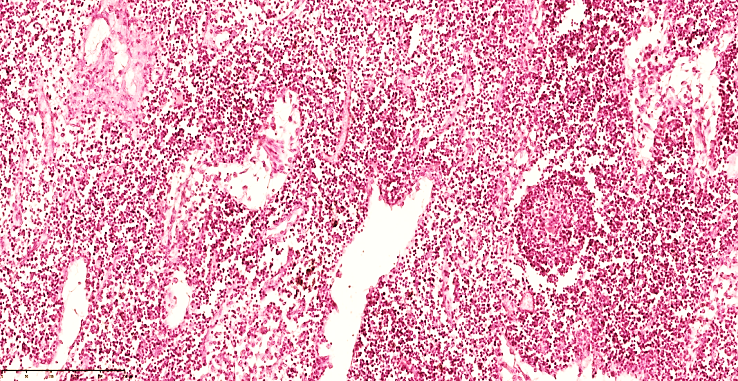

In the paracortical areas, a small number of T-lymphocytes are found, and in the space around the vessels, destroyed and various cell fragments are found. This fluid moves directly to the regional lymph nodes. The lymph node capsule is tense, of uniform thickness, macrophages are relatively reduced in the subcapsular space, lymphocytes are detected.Postcapillary venules were full-blooded, with foci of free lymphocyte migration in the focus. The perimeter of the postcapillary venules was covered with fibrinoid thickening.It was found that the histiotopographic shape of the lymph node was deformed in the areas of thickening and destruction of the trabecular stroma components, and the morphofunctional parameters of the lymph node were out of whack.Lymphostasis in the lymph nodes, lymphothrombosis, lymphadenitis in the lymph nodes, delymphatization and the development of foci of neutrophil infiltration in the postcapillary venules, complete blockage of the lymphatic drainage system in the lymph node, leading to the development of secondary complications (sepsis, septicemia, septicopyemia, etc.).Degranulation of mast cells in the microcirculatory bed, as a result of which plasmorrhagia and leukodiapedesis are enhanced, leading to the formation of inflammatory infiltrates in the parietal and visceral layers. (See Fig. 5, 6). As a result, venous congestion occurs, which leads to the development of interstitial edema and a sharp functional strain of the drainage system in the lymph nodes, which leads to lymph node enlargement and lymph node edema (See Fig. 7). | Figure 5. Mesenteric lymph node of a 28-day-old infant with peritonitis. In the cortical area, lymphocytes and plasma cells are reduced, lymphoblasts are increased with nucleoli, and stroma is disrupted. Delymphatic foci are detected. Staining G.E. Size 40x10 |

| Figure 6. Mesenteric lymph node of a 28-day-old infant with peritonitis. Treated on the 3rd day. In the cortical area, lymphocytes and plasma cells are reduced, mononuclear lymphoblasts are increased, and stroma is disintegrated. In the form of a cone, foci of reticulocytosis are detected. Staining GE. Size 40x10 |